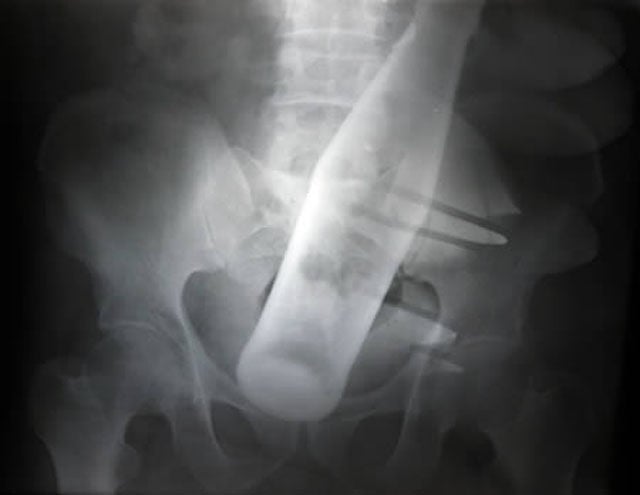

This X-ray was taken of a 60-year-old man who checked himself into Nishtar Hospital in Multan, Pakistan. He sought treatment because he claimed thieves had inserted a Pepsi bottle into his anus before stealing two of his buffalo.